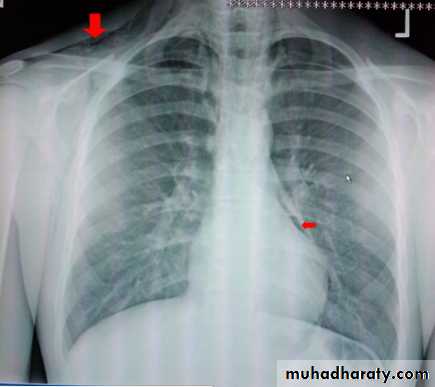

Pneumomediastinum : Air in the mediastinum indicates a tear in the oesophagus or an air leak from a bronchus (provided the air has not tracked into the mediastinum from the root of the neck, adjacent chest wall or retroperitoneum). These tears may be spontaneous or follow trauma, most commonly from endoscopy, following forceful vomiting (Boerhaave’s syndrome) or the ingestion of sharp foreign bodies Spontaneous leakage from small bronchi in the lungs is most commonly seen in patients with asthma.

The air, which tracks through the interstitial tissues of the lung into the mediastinum, is seen as fine streaks of transradiancy within the mediastinum, often extending upward into the neck.

Pneumomediastinum